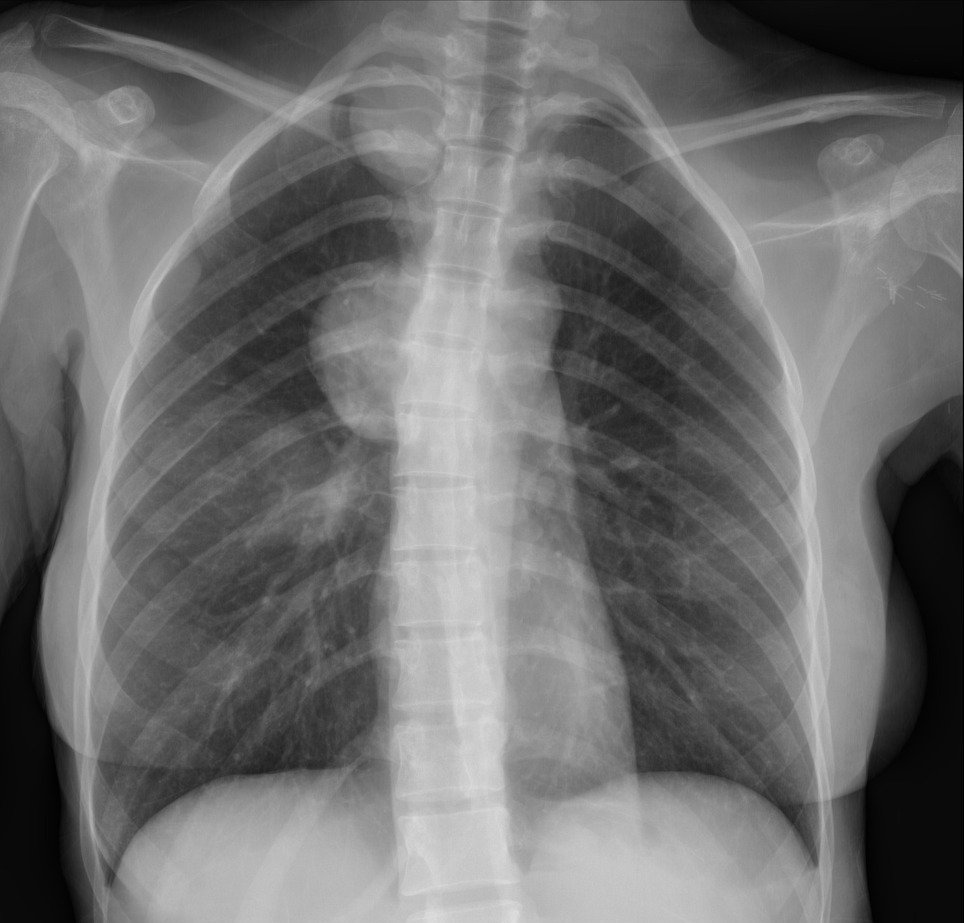

U trung thất là một khối u bất thường xuất hiện ở vùng trung thất của cơ thể, gây ra nhiều biến chứng và ảnh hưởng đến sức khỏe của người bệnh. Việc điều trị u trung thất phụ thuộc vào nhiều yếu tố như vị trí, kích thước và tính chất của khối u. Dưới đây là những thông tin cần biết về điều trị u trung thất.

U trung thất cần được điều trị sớm vì nếu không can thiệp, khi khối u phát triển, chúng sẽ chèn ép các cơ quan và mô. Các khối u trung thất nếu không được điều trị có thể phát triển nhanh gây ảnh hưởng nghiêm trọng đến sức khỏe người bệnh. Bệnh nhân dù có bị u trung thất lành tính hay ác tính thì đều có nguy cơ gặp biến chứng nếu không được điều trị kịp thời. Phần lớn những khối u phát triển trong trung thất đều được chỉ định áp dụng kỹ thuật sinh thiết, cắt bỏ, hoặc điều trị bằng xạ trị, hoá trị nếu phát hiện đó là các tế bào ung thư. Phẫu thuật là biện pháp điều trị cơ bản cho các khối u trung thất, đặc biệt khi có dấu hiệu chèn ép và xảy ra biến chứng, ảnh hưởng đến đường thở của bệnh nhân.